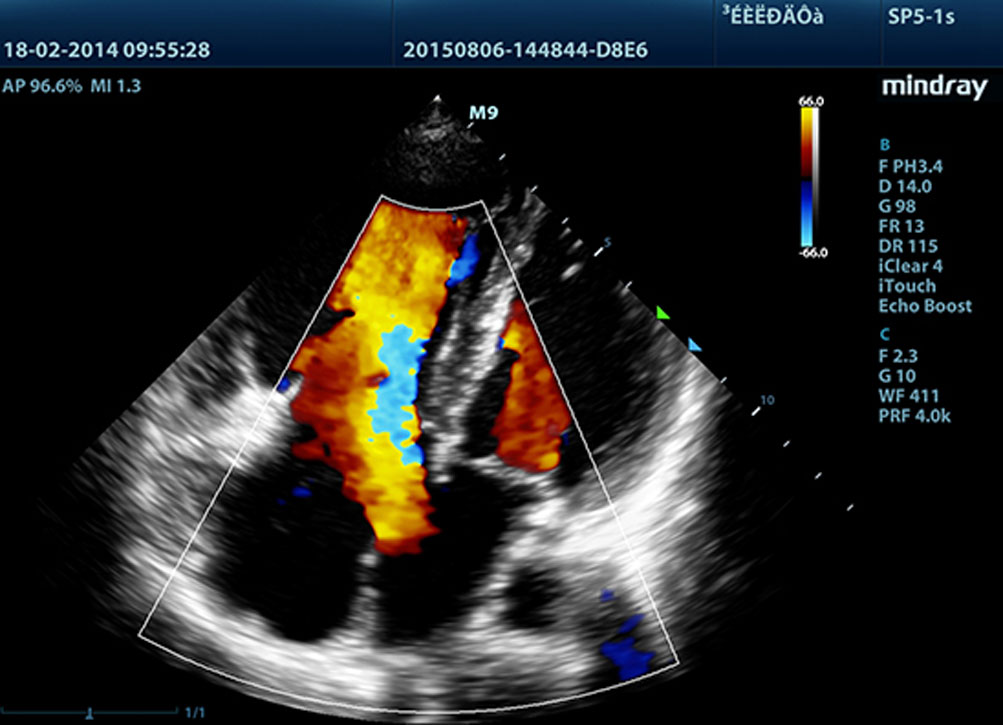

Daha belirgin g?rĂŒntĂŒler sa?layan, M9 ile uyumlu tĂŒm problar Mindray'in benzersiz 3T prob teknolojisiyle teslim edilir. Single crystal teknolojisinin eklenmesiyle gĂŒcĂŒ artan M9, ?zellikle zorlu hasta taramas? s?ras?nda daha iyi penetrasyon ve dinamik renk ak??? olana?? sunar.

?evredeki parazit gĂŒrĂŒltĂŒleri bast?r?rken gĂŒ?sĂŒz eko sinyallerini art?rmak i?in ba??ms?z sinyalden-gĂŒrĂŒltĂŒye bilgisini kullanmak ĂŒzere tasarlanm?? ak?ll? eko tespit ?zelli?i ile Mindray'in benzersiz uyarlanabilir sinyal i?leme teknolojisi, daha dengeli g?rĂŒntĂŒ parlakl??? ve miyokard doku katmanlar?n?n daha iyi g?rĂŒntĂŒlenmesini sa?lar.

iBeam?

Art?r?lm?? kontrast ??zĂŒnĂŒrlĂŒ?ĂŒ ve geli?mi? g?rĂŒntĂŒleme imkan?na kavu?ulan tek bir g?rĂŒntĂŒ olu?turmak i?in bir?ok tarama a??s?n?n kullan?lmas?na izin verir.